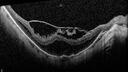

Stable Myopic Tractional Maculopathy15 views73 year old female with mild vision loss from table myopic tractional maculopathy in the left eye

Stable Myopic Tractional Maculopathy14 views73 year old female with mild vision loss from table myopic tractional maculopathy in the left eye